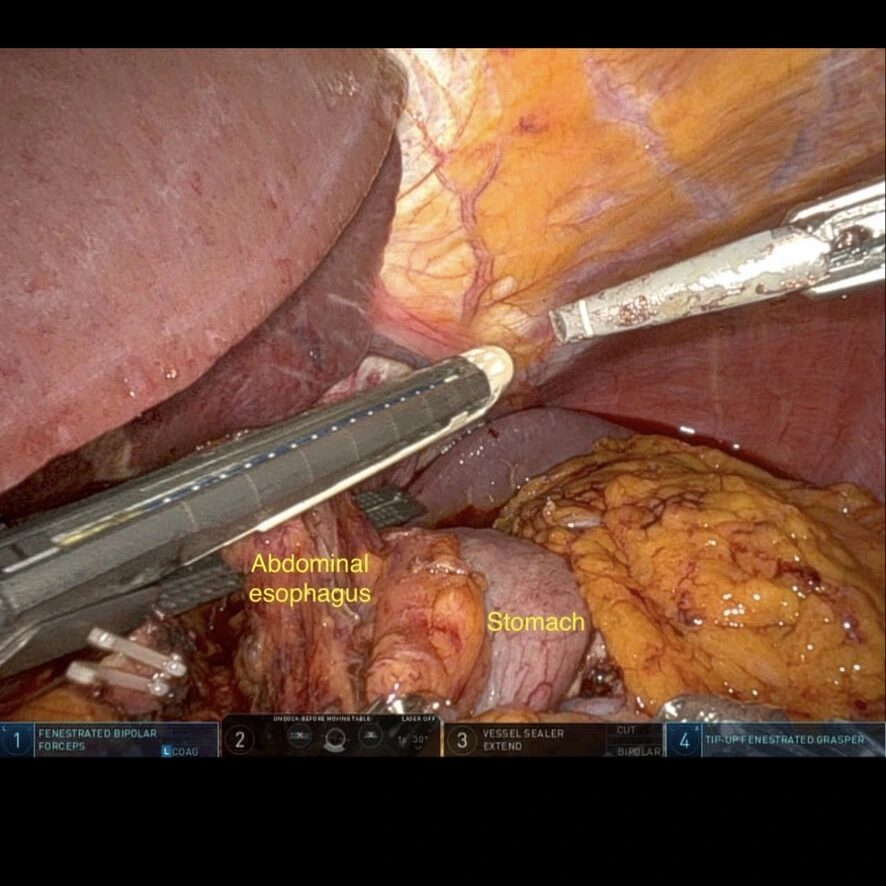

- Secționare esofag cu stapler liniar, cartuș alb;